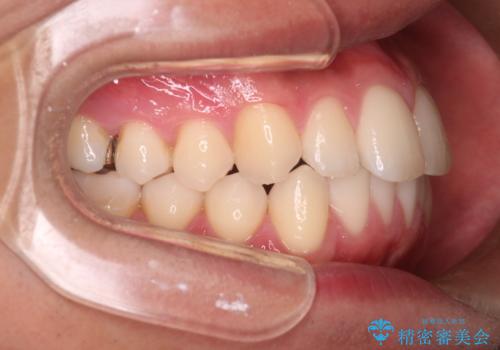

【インビザラインモニター】前歯が出ているのが気になる

- 上の前歯が出ているのが少し気になるとの事で来院されました。

インビザライン希望のため、IPR(歯と歯の間を削る処置)を行うことで、前歯の位置とがたつき整える治療計画を立てました。

患者様よりシュミレーション通りに歯が動くか心配との事だったので

出来るだけ計画通りに歯を動かすために、マウスピース1枚あたりの使用時間を長めに使っていただきました。

そのため、多少治療期間が延びましたが、リファイメント(マウスピースの再発注)なしで終了することができました。